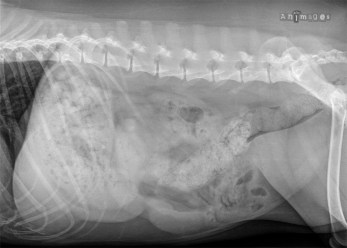

Cas intrigant 4 – Une masse abdominale ?

Signalement: chienne Airedale stérilisée de 7 ans

Présentation clinique: douleur abdominale soudaine